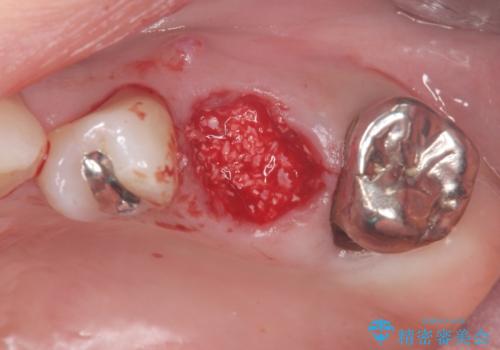

抜歯時に骨移植材を填入することで、抜歯後に大きく歯ぐきのボリュームが失われることを防ぎます。

歯ぐきのボリュームが保たれることで、清掃性の高いブリッジ治療を行うことが可能になります。